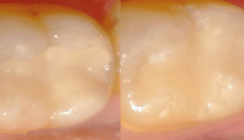

Für die Untersuchung griffen die Forscher auf Zähne aus Zirkonkeramik zurück. Diese wurden standardmäßig als Klasse II-Kavitäten präpariert und anschließend als Modell genutzt (Abb. 1). Insgesamt wurden auf diese Weise 24 Modelle hergestellt, von denen jeweils sechs den vier verschiedenen Testgruppen zugeordnet wurden. Die Restaurationsmodelle der einzelnen Testgruppen wurden in der Folge mit jeweils einem der zu untersuchenden Materialien – EQUIA Forte (GC), EQUIA (GC), Ketac Molar (3M ESPE) und IonoStar Molar (VOCO) gefüllt (Abb. 2). Zu diesem Zweck wurde zunächst ein Teilmatrizensystem angelegt; anschließend erfolgte die Applikation der Materialien gemäß den jeweiligen Herstellerangaben. 24 Stunden vor dem eigentlichen Bruchtest wurden die Restaurationsmodelle nun bei 100%iger Luftfeuchtigkeit und einer Temperatur von 37 Grad Celsius aufbewahrt. Anschließend belasteten die Wissenschaftler die Modelle mit einem Pressstab (Durchmesser 1,5 mm) mit einem Kraftaufnehmer (1 kN; Abb. 3). Die Traversengeschwindigkeit betrug 1 mm/min. Bei allen Proben kam hier-für eine universelle Prüfmaschine (LRX, Lloyd Instruments) zum Einsatz. Für die statistische Datenanalyse wurde schließlich auf eine einfache Varianzanalyse (ANOVA) und den Tukey HSD Post-hoc-Test zurückgegriffen.